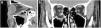

These are the second most common fractures of the facial skeleton after nasal fractures, because the mandible is a prominent bone and the only mobile bone in the facial region.16 They are important from an anatomical, aesthetic and functional point of view, as they affect activities such as chewing and speech.

The following units are distinguished in the mandible: condyle (with head, neck and subcondylar region), coronoid process, ramus, angle, body, symphysis and parasymphysis region (separated by from the body by an imaginary line drawn from the canines), alveolar process (where the teeth are found) and basal segment (along the lower margin of the mandible). The angle of mandible is delimited above by the region of the third molar and below by the area of the inferior insertion of the masseter muscle (Fig. 9).

(A) 3D representation of the mandibular units. Coronoid (Cr), condyle (Cd), ramus (R), angle (A), body (B), symphysis (S), alveolar process (Av) and basal segment (BS). (B and C) 3D reconstruction. Fracture of the occluding segment of the maxilla with dentoalveolar involvement and marked displacement of the fragments (asterisk). Fracture of the mandibular symphysis (arrow) and both condyles with impaction (arrow tips). (D) 3D reconstruction. Bilateral fracture of the body of the mandible with marked posterior displacement of the free fragment and risk of compromising the airway.

The mandible has a characteristic U-shaped morphology and articulates with the skull via the synovial temporomandibular joints (TMJ), forming a ring-shaped structure that is the reason for the presence of two fracture lines after trauma. Occasionally, only one fracture is identified as some of the force of the impact dissipates through the TMJ.45 Fracture and luxation of the TMJ can also occur, and should be reduced prior to imaging.16 A high percentage of mandibular fractures are associated with one direct mechanism causing a fracture line at the site of the impact, and a second indirect mechanism due to transmission of the energy, with another fracture line at some distance from the initial impact.

The condyle is often the most affected region due to its structural weakness, and almost half of these fractures are caused by an indirect mechanism and associated with another type of mandibular fracture, commonly in the symphyseal or parasymphyseal region.17 In mandibular condyle fractures with displacement, this is often towards the midline due to the traction of the lateral pterygoid muscle that inserts at the head of the condyle. Sagittal fractures of the head of the condyle go unnoticed as they have no repercussions on eventual occlusion. Approximately 40% of mandibular fractures have more than one line1 and most affect both the superior and inferior mandibular buttresses.16